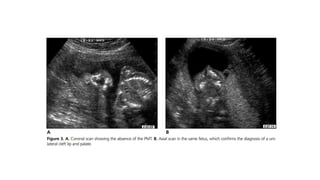

• intact skin line of the upper

lip (no cleft).

• Behind this is an echogenic

intact hard palate; this

confirms the correct plane,

and is useful to distinguish

palate involvement if a

cleft lip is present.

• intact skinline of the upper lip (no cleft). • Behind this is an echogenic intact hard palate; this confirms the correct plane, and is useful to distinguish palate involvement if a cleft lip is present. • The hard palate has internal areas of reduced echogenicity representing tooth sockets.